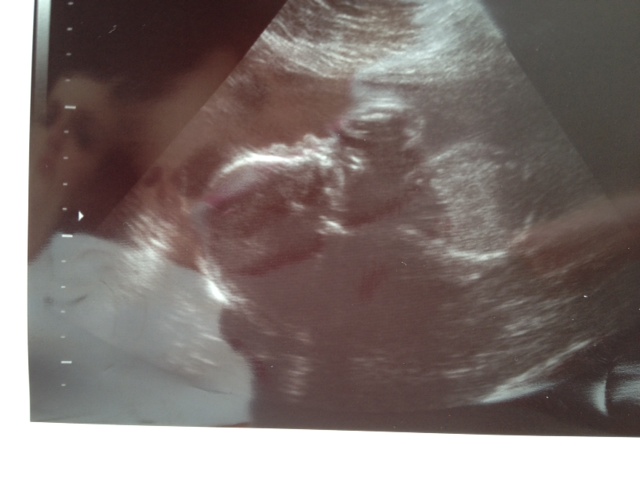

Lillian 24 weeks

HR: 141

I am so shocked that I am already 24 weeks pregnant. Huge milestone in the NICU world. Offically viable! Of coarse we want her to stay put for 16 more weeks but this is the point where mommy starts to see babies in the NICU the same size as Lillian. We are so fortunate that things are still going great. This pregnancy has been a little harder on my body but I am hanging in there. Maybe it's because I am older or maybe because Brad is traveling alot and I am a full time mommy who knows but I am exhausted most days. I am having a lot of Braxton hicks contractions which I didn't have many of with Harper and still having trouble with the sciatic nerve issue . Some days it is really bad and some days I do great. Other than that I feel great. I have been working in Lillian's room. This week I cleaned out the closet of Harper's old stuff and organized the new stuff. I went through all of Harper's clothes and organized it all by dates so it is easy to use for the new baby. Wow ,these girls are so spoiled. So now we set up the furniture and ordered the bedding. I still need to take down Harper's old decals and take down the shelving but we are making progress slowly. I had my glucose test last week and passed with flying colors. YEAH... This means I can continue my sugar fest!!! And we had our follow up low placenta sono and my placenta has moved up so it is no longer a potential problem. As usual Lillian was so precious on sono. She had her hands in her mouth most of the time and in one picture she was sucking on her fingers. And we took Harper to this appointment and every time she would be loud, Lillian would move. This was the first appointment Harper had been to and it was a bit challenging but she was able to meet Dr. N for the first time since she was a newborn. Also Lillian is measuring 26.5 weeks in length which made us giggle a little. Brad and I are so short it surprises me that she is measuring tall for her age. Maybe she will be tall like Mimi and uncle Mike. Here are a few picture of our sweet girl and a few of her room so far. 24 week belly shot! Harper's first appointment to see Lillian! Lillian's closet and new furniture! My sweet Lillian...